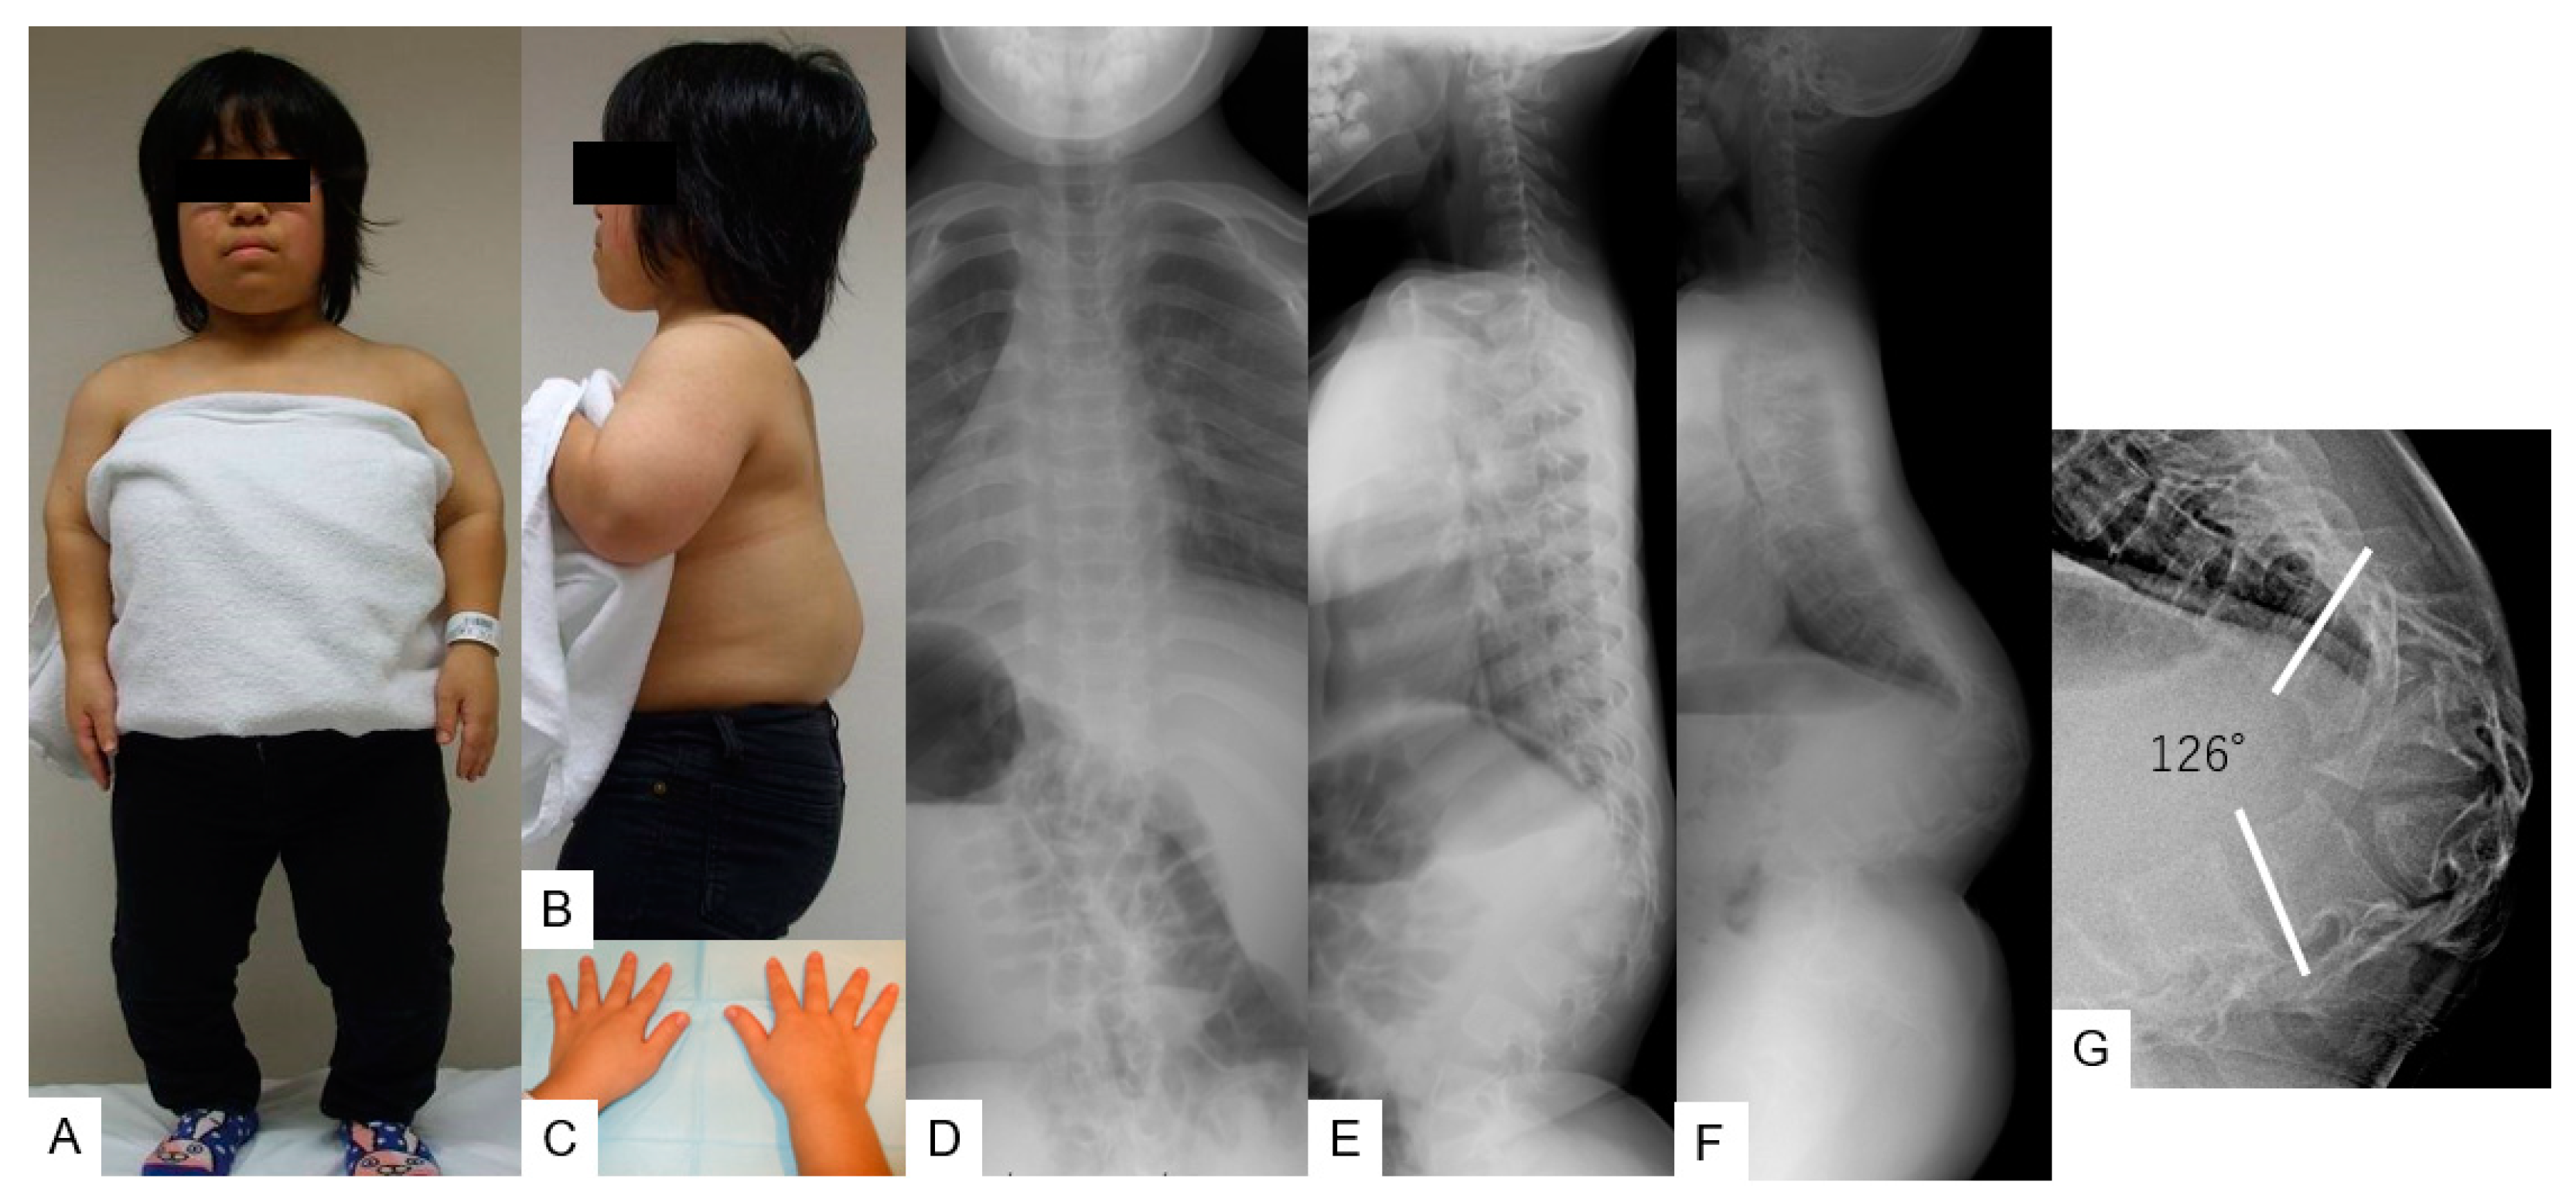

3.1. Case 1—16-Year-Old Girl, Achondroplasia, Thoracolumbar Kyphosis 126°

3.1.2. Physical Examination

3.1.3. Preoperative Imaging